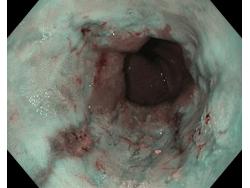

Choroba refluksowa